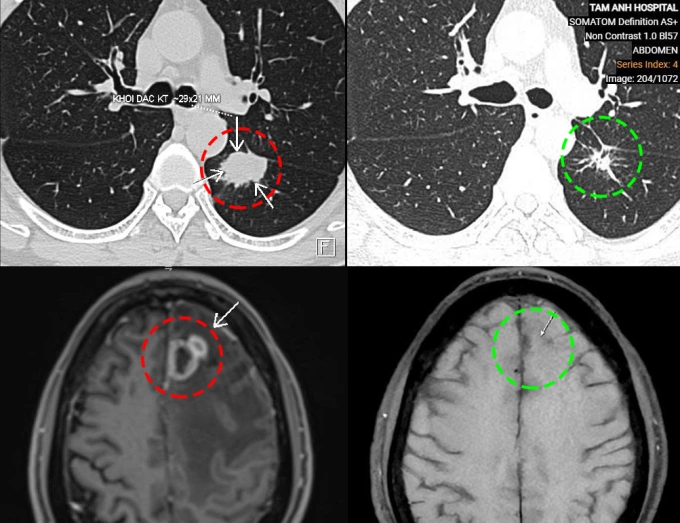

TS.BS Vũ Hữu Khiêm, Trưởng khoa Ung bướu, Bệnh viện Đa khoa Tâm Anh Hà Nội, cho biết ông Chung đến khám lần đầu vào nửa năm trước trong tình trạng yếu liệt nửa người, đi lại khó khăn, đau đầu, chóng mặt, tức ngực, khó thở. Kết quả xét nghiệm máu, chụp cộng hưởng từ não (MRI) và chụp cắt lớp vi tính (CT) ngực cho thấy khối u kích thước 21×29 mm ở thùy dưới phổi trái và khối u kích thước 30x24x21 mm ở thùy trán não trái, kèm phù não rộng xung quanh.

Ông Chung đáp ứng tốt với điều trị. Kết quả chụp MRI và CT sau 6 chu kỳ truyền thuốc miễn dịch cho thấy cả khối u thùy dưới phổi trái và khối u di căn não đều đã giảm kích thước. Tổn thương phù não không còn. Người bệnh hết đau đầu, chóng mặt, hết yếu liệt nửa người, tiếp tục duy trì phác đồ cho đến khi bệnh khỏi hoàn toàn.